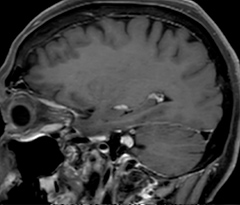

This is an example of acute ischemic stroke with distal occlusion of the right posterior cerebral artery. Note the improved visibility of the ischemic territory on the diffusion weighted image with high b-value. The 3D FLAIR shows a distal PCA occlusion. The fast SWIp depicts the thrombus on the isolated second echo image. The total scan time (including SmartBrain, preparations and a fast 3D T1w TSE Gd) is 8:00 minutes.

Acute right motor deficit and aphasia

In this patient with acute right motor deficit and aphasia, the b2000 diffusion weighted image is normal. The SWIp image demonstrates more prominent veins in the right hemisphere, which could reflect increased deoxyhemoglobin contents. Fast ASL shows low CBF regions in the left frontal lobe. A follow-up ASL after one hour demonstrates high CBF values in the same area. The final diagnosis was migraine with aura.